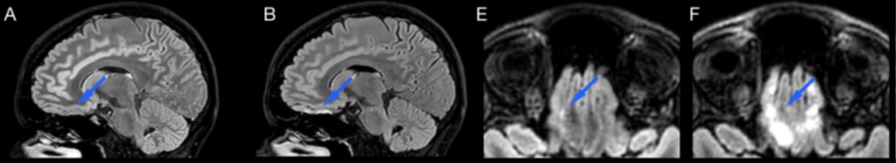

6/9 👥 Human imaging (n = 14 across multiple conditions): C-FLAIR removed skull-base hyperintensity artifacts while preserving lesion visibility in MS and white matter disease ✅ 🩻Key Clinical Point: • SNR unchanged • CNR unchanged

3/9 This is especially noticeable at 3T 🎛️ Skull base, sinuses, and temporal bone regions are notorious for off-resonance and RF variation → where FLAIR is often least trustworthy. Here, the B, F images are acquired without T2-preparation to better expose the FLAIR artifact.